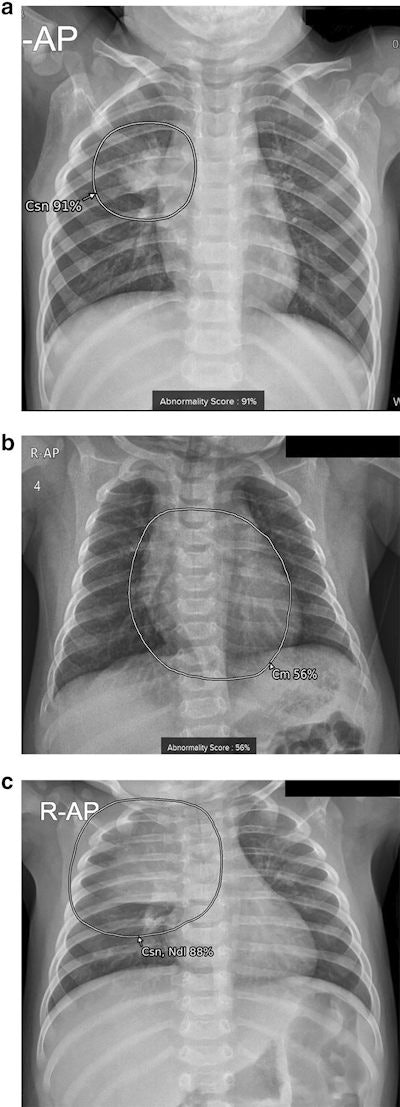

The algorithm was tested first for identifying eight detectable lesions: nodules, consolidation, fibrosis, atelectasis, cardiomegaly, pleural effusion, pneumothorax, and pneumoperitoneum. In these cases, the software achieved an accuracy of 87.5%.

Next, the researchers excluded cardiomegaly (enlarged heart), given that different criteria are used to diagnose the condition in adults and young children, whereby the software achieved an accuracy of 89.5%.

In addition, the researchers found that images with incorrect diagnoses by the software were significantly younger than patients with correct diagnosis. When they excluded children 2 years old and younger from the analysis, the software's accuracy increased up to 96.9%, which was comparable to the diagnostic accuracy provided by the vendor for adults, the researchers wrote.